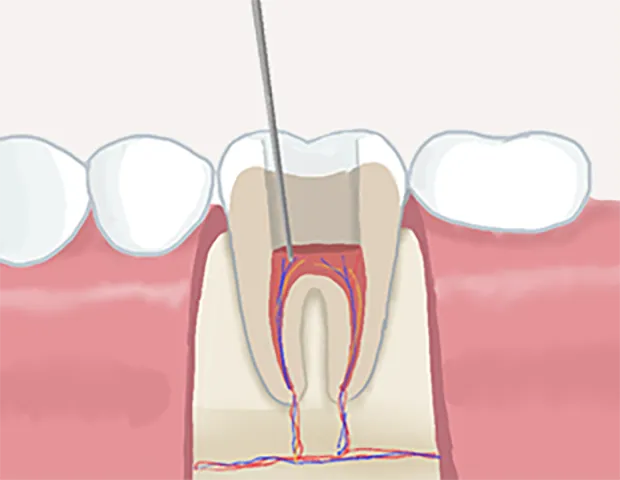

根管治療とは歯の根っこにある歯髄と呼ばれる神経や血管が通っている細い管状の部分である根管の中にある「虫歯に感染した歯の神経」「細菌」「過去に詰めた古い充填材」等を除去していく治療法です。細菌に侵された部分を丁寧に除去・消毒・洗浄を行い、薬液を充填して歯を温存します。

根管治療の流れ

• 根管内の洗浄

3根管内の洗浄

根管内を薬液で洗浄消毒して、細菌を隅々まで取り除きます。